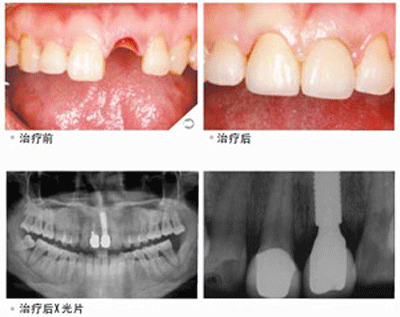

患者的口腔状况良好,牙槽骨状况适合做种植牙。因为种植牙是把人工牙根植入牙槽骨内来代替真牙牙根,然后在人工牙根上制作烤瓷牙冠,完成时对缺失牙齿的修复的。如果患者的牙槽骨状况不佳的的话,比如牙槽骨的宽度和高度不够的话则需要考虑做植骨手术。

(1)单颗缺牙时不需要磨损两侧真牙,单颗牙种植体值入后,以烤瓷牙冠修复,特别是末端游离的后牙,传统的固定和活动义齿均难以修复;(2)多颗缺牙,多颗牙种植体植入后,上部烤瓷牙整体修复,稳定性和功能与真牙相似。(3)全口缺牙,多颗牙种植体植入后,当做支柱,以制作覆盖义齿,使其很稳定舒适。